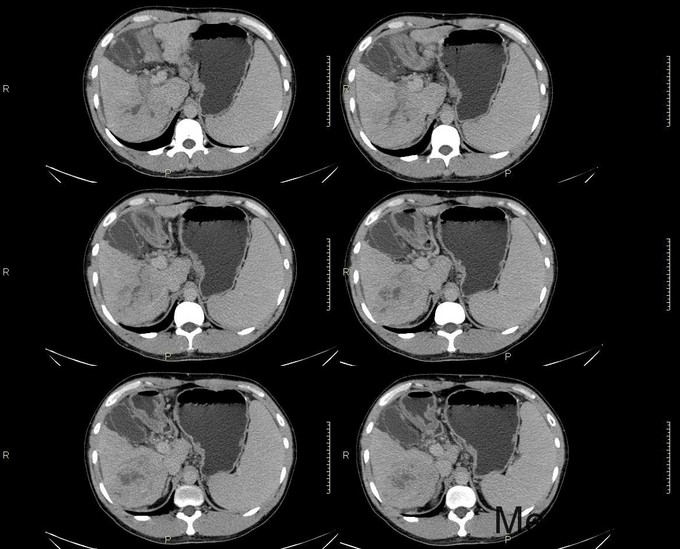

主诉:反复乏力、纳差2月余。身目黄染1月余。 病史:患者中老年男性,2月前出现乏力、纳差,查乙肝两对半示大三阳,上腹部CT示肝硬化,予护肝等治疗后好转出院。1月前天前出现身目黄染,伴瘙痒,再次入院。 既往史:患者有肝癌家族史(父亲肝癌去世)

查体:慢性肝病体征,肝掌阳性,蜘蛛痣阳性,胸前毛细血管扩张,腹水征阳性,肝脾肋下可触及。 辅查:生化:谷草146,谷丙110,总胆184,直胆114,白蛋白38,凝血四项:PT17.9s,PTA56。 CA-125: 600,CA-199:54.13,AFP:98.73。 肝彩:1、肝硬化,肝左叶可见高回声团。 上腹部CT: 肝癌、肝硬化、脾大

诊断:1、原发性肝癌;2、乙肝肝硬化 1、常规护肝退黄降酶,输血浆,护胃制酸等对症支持治疗 2、转肝脏外科。